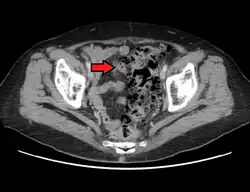

- Contrast CT is the investigation of choice in acute episodes of diverticulitis and where complications exist.